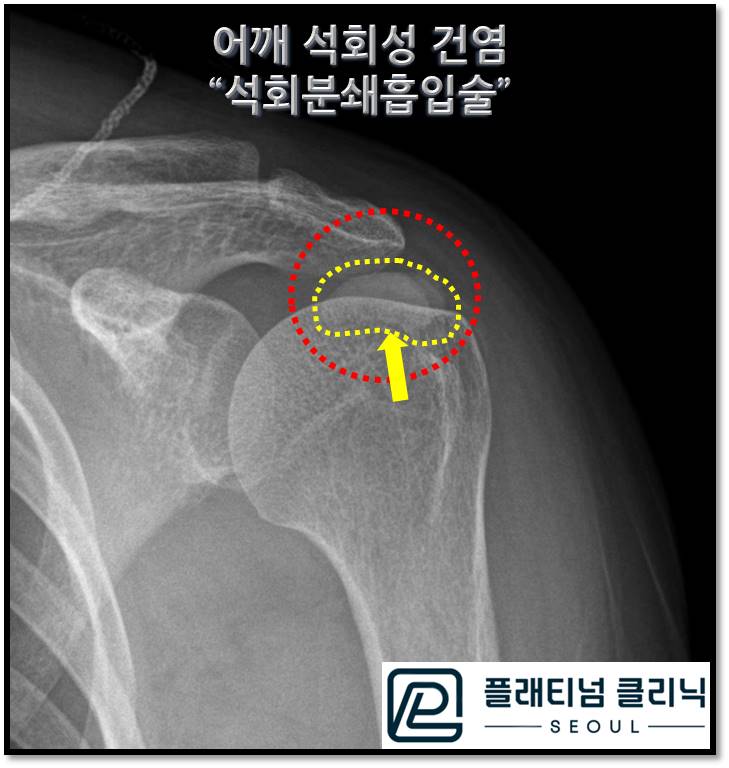

석회성건염 치료 한번에 해결됩니다.

안녕하세요. 정형외과 전문의 이동규 원장입니다. 오랜만에 글을 쓰게 되네요. 여러가지 준비를 하느라 이...